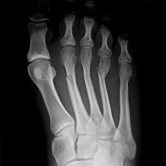

Röntgenbilder